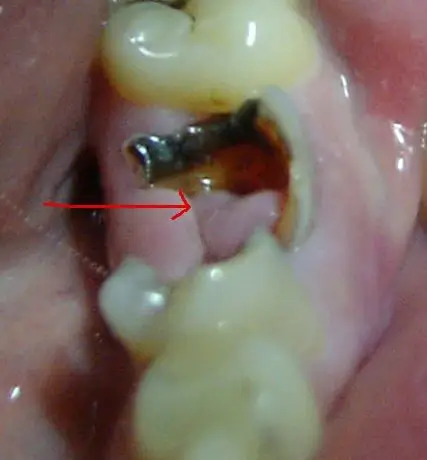

看来是你的牙龈组织长出来的息肉,到医院想办法处理一下,很小的手术